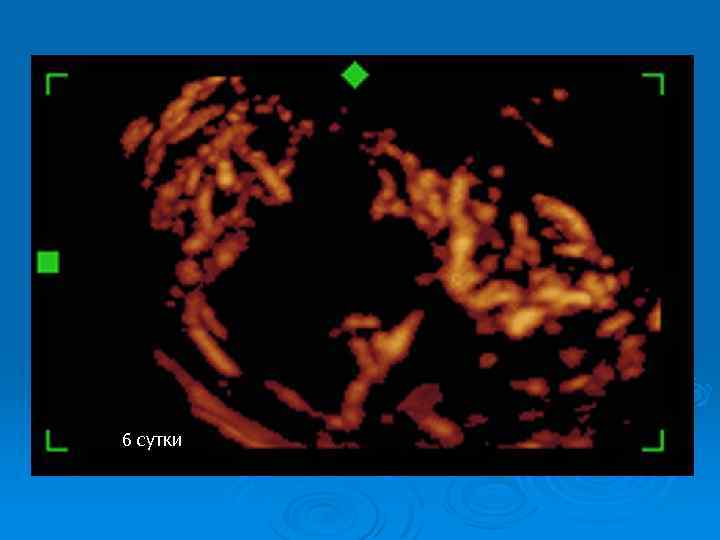

До операции: перекрут 1100 градусов, 14 часов

6 сутки

Перекрут яичка: наблюдение в динамике Ø Регулярный УЗИ контроль Ø Оценка гормонального статуса Ø Исследование эякулята